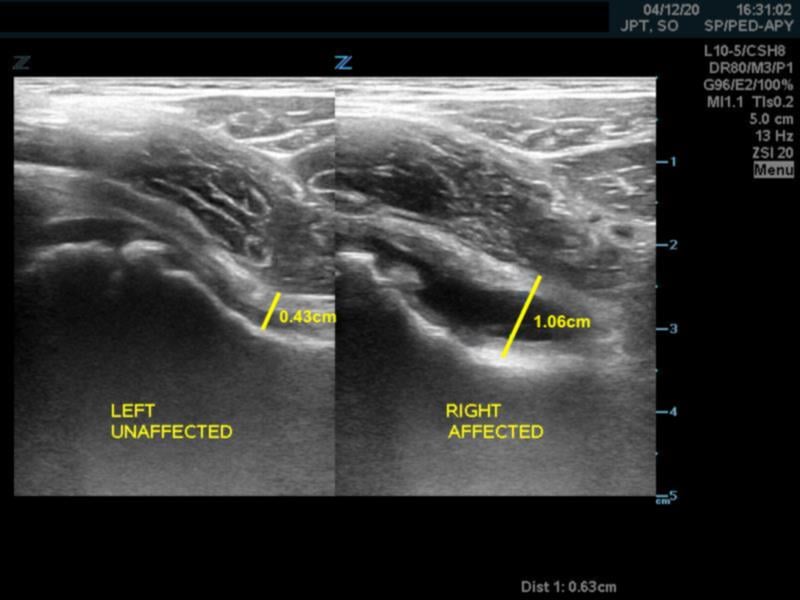

- A capsular-synovial thickness >5 mm, or >2 mm difference compared to the asymptomatic contralateral side indicates hip joint effusion in children

- Figure 4. Capsular-synovial thickness measurement >5mm in hip effusion (right)